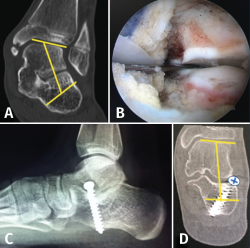

Coalición tarsiana

La coalición tarsiana es una deformidad del pie causada por la unión fibrosa, cartilaginosa u ósea entre huesos del tarso. La incidencia estimada es del 1-2% en la población general, siendo la coalición calcaneonavicular (CNC) la forma más frecuente (53%), seguida de cerca por la TCC.

La forma de presentación es un PPV rígido doloroso con historia de esguinces de repetición, con predominio de dolor al nivel del seno del tarso en supinación si es CNC y de dolor medial con deformidad en valgo más acusada en caso de TCC.

El tratamiento quirúrgico consiste en realizar la exéresis de la coalición de forma abierta con interposición de tejido. El tratamiento moderno consiste en resecar por vía endoscópica la CNC(17) o la TCC(18), sin interposición de tejido. La rápida movilización evita la recidiva. En caso de PPV de más de 20° se puede asociar el tratamiento del calcáneo stop, tras la resección de la coalición(18)(Figura 16).

Figura 16. A: valgo severo de retropié secundario a coalición talocalcánea; B: tras resección completa por vía artroscópica de la coalición, se verifica la movilidad subastragalina, al realizar varo-valgo del talón; C: colocación de calcáneo stop, para corregir el valgo del retropié; D: tomografía axial computarizada de control, donde se visualiza resección de la coalición y corrección del valgo del retropié.

En el caso de PPV secundarios a TCC irresecables, se puede realizar una osteotomía de alargamiento del calcáneo (columna externa)(8).

Como última opción, en sinostosis irresecables y/o con signos radiológicos de degeneración articular, se puede plantear realizar artrodesis subastragalina o una triple artrodesis.